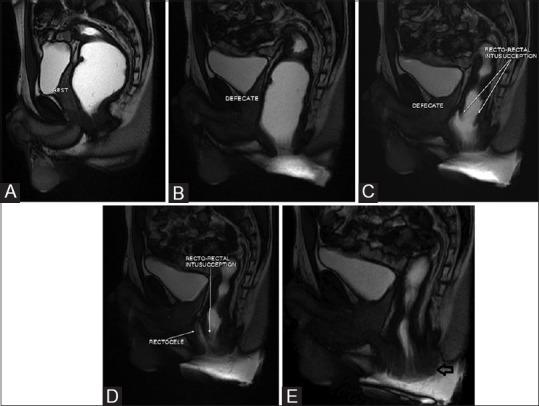

用于排便障碍综合征的磁共振排粪造影

MR defecography for obstructed defecation syndrome.

Patients with obstructed defecation syndrome (ODS) form an important subset of patients with chronic constipation. Evaluation and treatment of these patients has traditionally been difficult. Magnetic resonance defecography (MRD) is a very useful tool for the evaluation of these patients. We evaluated the scans and records of 192 consecutive patients who underwent MRD at our center between January 2011 and January 2012. Abnormal descent, rectoceles, rectorectal intussusceptions, enteroceles, and spastic perineum were observed in a large number of these patients, usually in various combinations. We discuss the technique, its advantages and limitations, and the normal findings and various pathologies.

摘要

排便梗阻综合征(ODS)患者是慢性便秘患者中的一个重要亚组。传统上,对这些患者的评估和治疗一直很困难。磁共振排粪造影(MRD)是评估这些患者的非常有用的工具。我们评估了2011年1月至2012年1月期间在我们中心接受MRD检查的192例连续患者的扫描结果和记录。在这些患者中,大量观察到异常下降、直肠膨出、直肠直肠套叠、肠膨出和会阴痉挛,通常是多种情况并存。我们讨论了该技术、其优点和局限性,以及正常表现和各种病变。